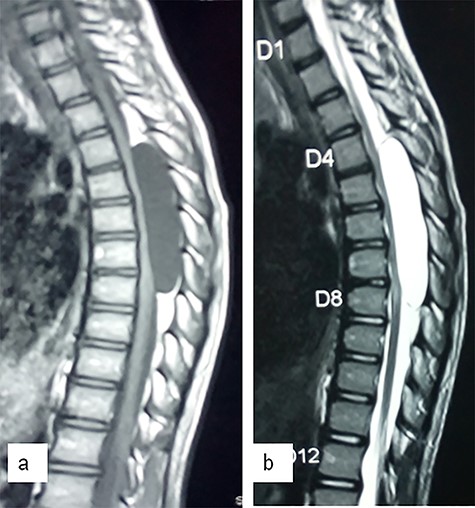

This 12-year-old girl presented with progressive lower limb weakness of eleven months duration, with associated spasms and paraesthesia. There was no back pain or sphincteric dysfunction. She was ambulating with crutches at presentation. Neurological examination revealed spastic paraparesis, with power grade 3–4 in most muscle groups of the lower extremities. Muscle stretch reflexes were brisk with un-sustained ankle clonus and extensor plantar response bilaterally. Thoracic spine MRI showed a cystic lesion compressing the spinal cord posteriorly from T4–T8 (Fig. 1). We performed a T4–T8 laminectomies and total excision of the cyst. The cyst communicated with the subarachnoid space through a pedicle located dorsolaterally at T7 close to the nerve sleeve (Fig. 2). The dura defect was repaired without duroplasty. There was no complication. She made remarkable post-operative improvement and was ambulating without support at the time of discharge. She was last seen at the outpatient clinic 18 months after surgery. The post-operative neurological improvement was sustained; the power was grade 5 in all muscle groups of the lower limbs (Fig. 3).

Sagittal T1 (a)- and T2 (b)-weighted MR images showing a large cystic lesion at T4–T8 compressing the spinal cord.